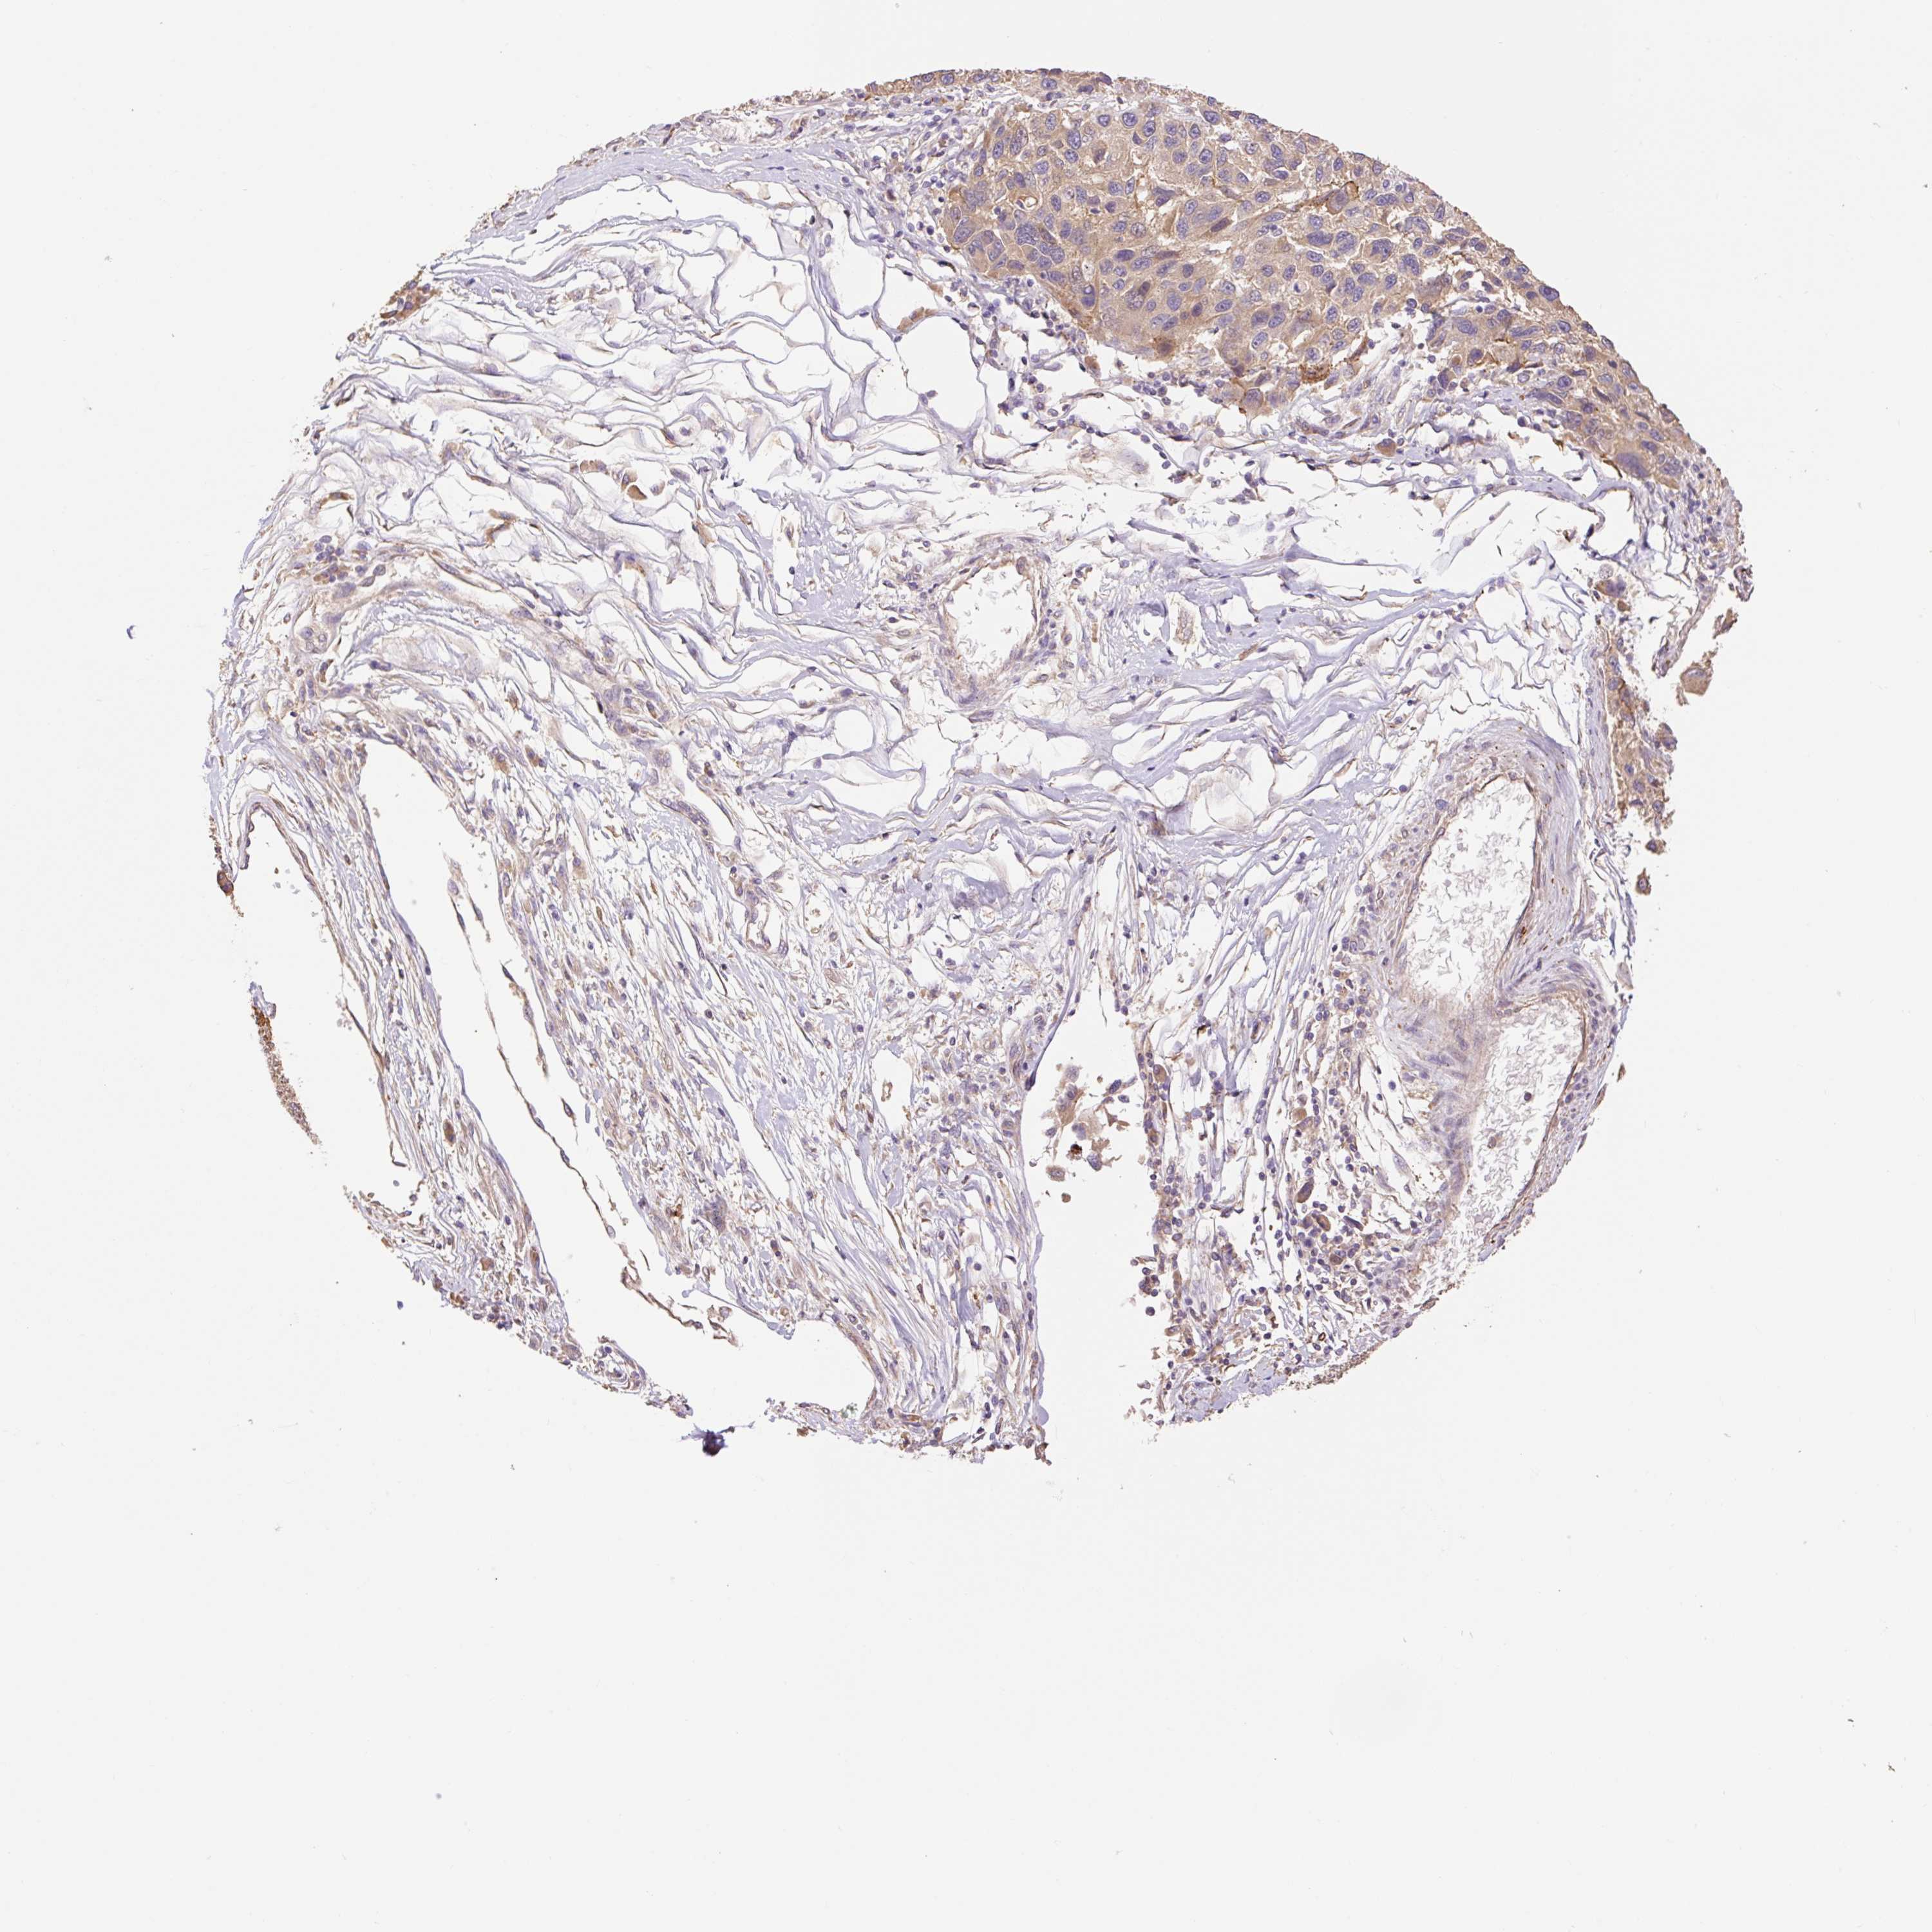

MELANOMA - Protein expressioni

A mouse-over function shows sample information and annotation data. Click on an image to view it in a full screen mode. Samples can be filtered based on level of antibody staining by selecting one or several of the following categories: high, medium, low and not detected. The assay and annotation is described here.

Note that samples used for immunohistochemistry by the Human Protein Atlas do not correspond to samples in the TCGA dataset.

Antibody stainingi

Antibody staining in the annotated cell types in the current human tissue is reported as not detected, low, medium, or high, based on conventional immunohistochemistry profiling in selected tissues. This score is based on the combination of the staining intensity and fraction of stained cells.

Each image is clickable and will lead to virtual microscopy that enables deeper exploration of all samples and also displays staining intensity scores, fraction scores and subcellular localization as well as patient and tissue information for each sample.

Antibody HPA053415

Malignant melanoma, NOS

Malignant melanoma, Metastatic site